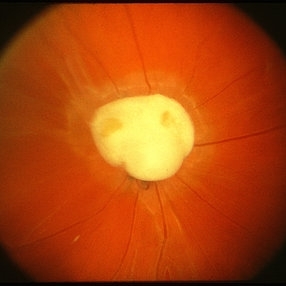

Toxocara Granuloma

Jun 4 2014 by Henry J. Kaplan, MD

Toxocara granuloma in the macula OS. #1

Condition/keywords: toxocara granuloma